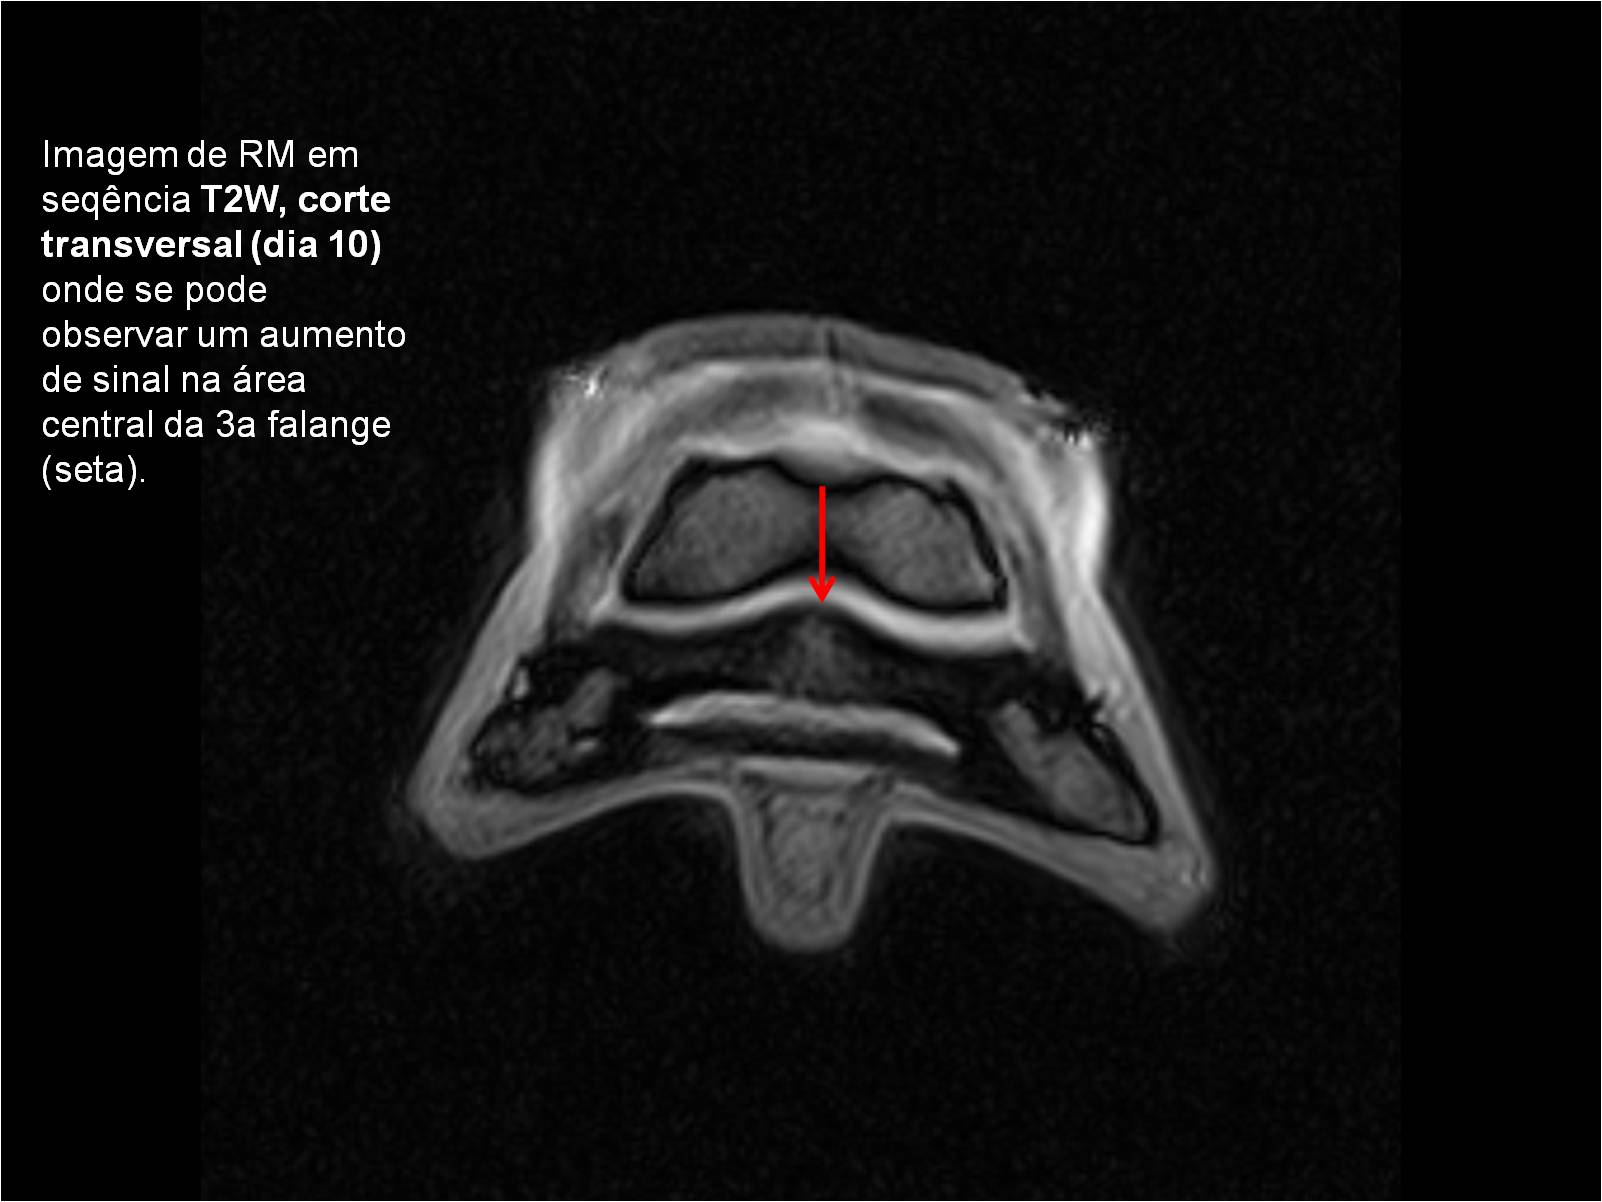

Publisher: Universidade de Évora

Abstract: O relatório de estágio encontra-se estruturado em três partes distintas. A primeira parte faz a caracterização das infraestruturas e funcionamento do Hospital Veterinário de Equinos de Lüsche, Oldenburg, Alemanha, assim como a análise casuística dos casos clínicos acompanhados durante os 6 meses de estágio. A segunda parte consiste de uma revisão bibliográfica sobre quistos do osso subcondral em equinos. Por fim, a terceira parte consta da apresentação e discussão de um caso clínico, nomeadamente o diagnóstico e acompanhamento imagiológico, por ressonância magnética, de um quisto subcondral na terceira falange num cavalo adulto; ### Abstract Equine Practice- Subcondral bone cyst of the third phalanx This internship report is divided in three parts. The first part characterizes the infrastructure and function of the Equine Hospital Lüsche, Oldenburg, Germany, as well as the casuistic of the clinical cases accompanied during the 6 month internship. The second part consists in a bibliographic review of cystic lesions of the subchondral bone in equines. The third part consists in a case report, the diagnostic and imagiological accompaniment, by use of magnetic resonance imaging, of a subchondral bone cyst in the distal phalanx of an adult equine.